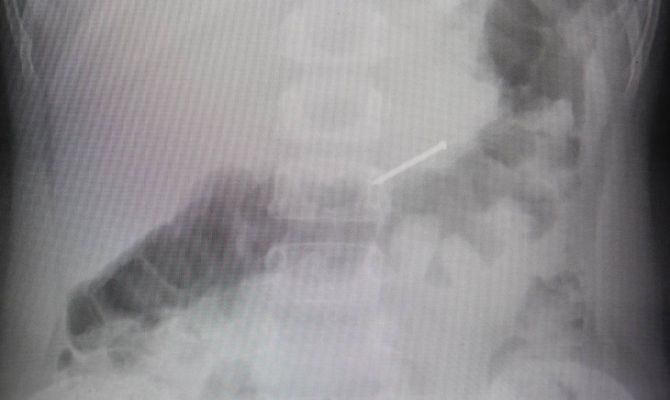

Названы неочевидные признаки, что ваш ребенок что-то проглотил

Чаще всего хирурги находят в ЖКТ пациентов монетки, магниты, крестики, драгоценности и гвозди